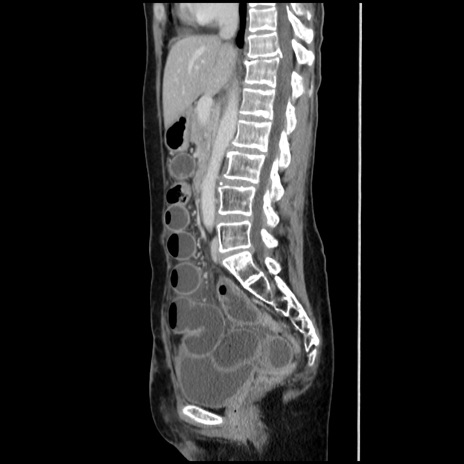

症例32(矢状断像)

【症例】40歳代 女性

【主訴】上腹部痛、嘔気・嘔吐

【現病歴】約9時間前頃から急に上腹部痛、嘔気、嘔吐が出現。改善しないため救急要請。

【既往歴】子宮頚癌(広汎子宮全摘術、放射線療法)、腸閉塞

【身体所見】腹部:平坦、軟、腸雑音亢進、上腹部を中心に腹部全体に圧痛あり。

【データ】WBC 8400、CRP 0.03